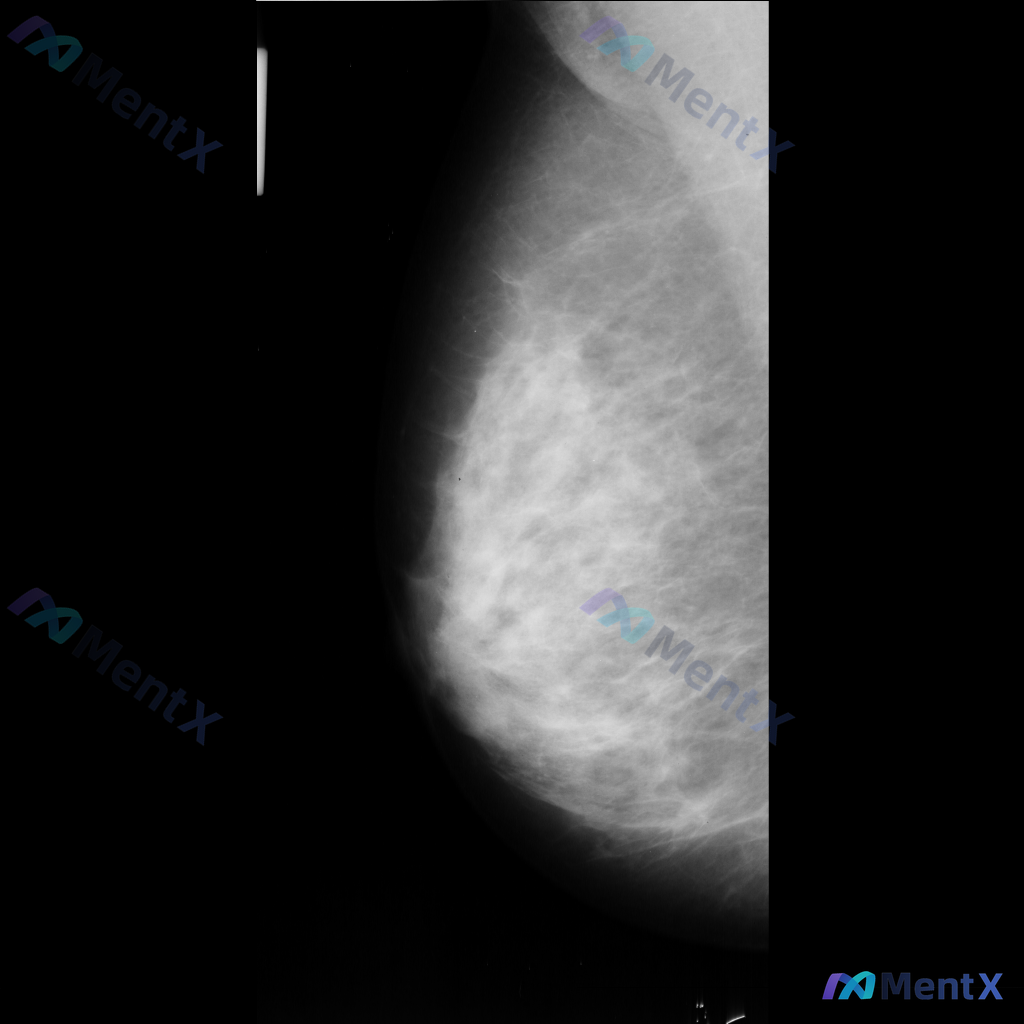

整理到一张单侧乳腺钼靶影像的相关描述,分享给大家讨论: - 乳腺背景:腺体组织呈不均匀致密型,脂肪与腺体交错分布 - 主要异常:影像中央偏下方可见一区域性致密影,边界模糊,与周围腺体融合,性质待查 - 其他征象:提及可见散在的、数量极少的细小点状钙化,但无法详细描述形态和分布 目前只有这一张单侧片的...